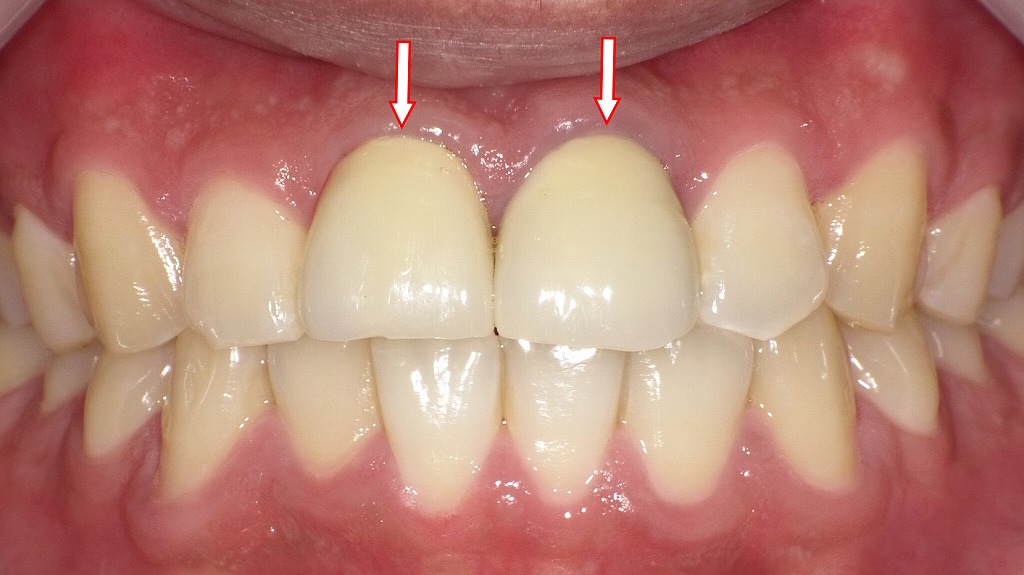

メタルボンドクラウンの装着

この画像は、前回の「圧排糸による印象採得」の症例の最終補綴後(完成形)を示しています。

中央の赤矢印が示すのは、上顎中切歯(右上1番・左上1番)に装着されたメタルボンドクラウン(陶材焼付鋳造冠)です。

🦷 症例の概要

この患者さんは、上顎前歯2本(中切歯)の被せ物を新しく作り直す治療を受けています。

前回の写真(支台歯形成+圧排糸装着)で型取りが完了し、その後に技工所で製作されたメタルボンドクラウンが装着された状態です。

🔍 メタルボンドクラウンとは

- 内側に金属フレーム、その上にセラミック(陶材)を焼き付けた構造の被せ物です。

- 金属の強度と、セラミックの自然な透明感を兼ね備えています。

- 前歯部では審美性が高く、色調調整も可能なため、保険適用外の高品質補綴として用いられます。

👀 画像のポイント

- 赤矢印の歯(上顎1番)は左右ともにメタルボンドクラウンが装着されています。

- 歯肉との境界(マージン部)は滑らかで、炎症や出血が見られず、適合性が良好。

- 隣接歯との形態・色調の調和もとれており、自然な仕上がりとなっています。

- 咬合も安定しており、中央の正中線もほぼ一致しています。

💡 まとめ

この画像は、

➡️ 上顎中切歯にメタルボンドクラウンを装着した最終補綴の状態を示しています。

圧排糸による精密印象から得られた高精度な模型をもとに、

審美性・適合性ともに優れた補綴が完成しており、

前歯部審美修復の成功例といえる症例です。